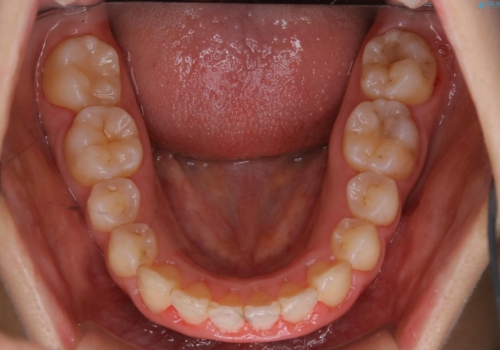

- 矯正装置

- ワイヤー審美装置

- 治療計画

- 4年ほど前から地元の歯科医院にてインビザライン治療を行っていたが、引っ越し後に通いづらくなってしまったため、治療が途中で止まってしまっているとの事で来院されました。性格的にインビザラインの継続した使用が難しいとのことで、ワイヤー装置にて最終仕上げを行いました。

治療について

インビザラインは20時間以上の装着を厳守して頂くことで治療効果が期待できる治療となります。固定式のワイヤー装置に切り替えることで短期間で歯並びを整えることができ、大変喜んでいただけました。